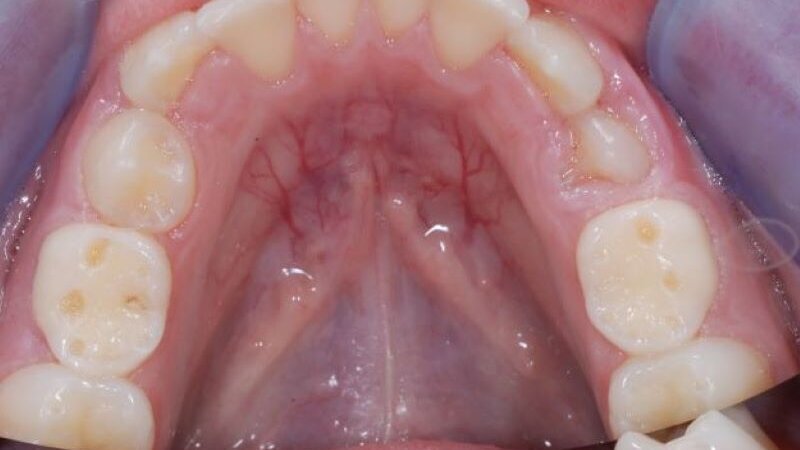

Slika 2. U ranoj fazi erozivnog trošenja, karakterističan je gubitak strukture vrhova kvržica u vidu formiranja konkavnih udubljenja (kod ovog pacijenta vidljivo je na drugim mlečnim molarima).

Rana dijagnostika erozivnog procesa može biti teška, imajući u vidu da većina pacijenata nema simptome, posebno kada je napredovanje procesa sporo i omogućava formiranje reparatornog dentina sa okluzijom dentinskih tubula. Rani klinički znaci su gubitak teksture gleđi, mat izgled površine gleđi, kao i gubitak strukture vrhova kvržica u vidu formiranja konkavnih udubljenja (Slika 2) (15). U kasnijim fazama dolazi do potpunog gubitka okluzalne morfologije i izravnjavanja okluzalnih struktura. Kada su prisutni ispuni, karakteristično je da jasno prominiraju u odnosu na okolne zubne strukture koje su zahvaćene erozijom.